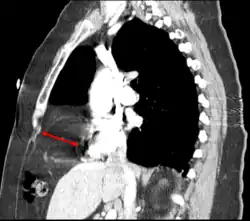

Bochdalek hernia

The Bochdalek hernia, also known as a postero-lateral diaphragmatic hernia, is the most common manifestation of CDH, accounting for more than 95% of cases. In this instance the diaphragm abnormality is characterized by a hole in the postero-lateral corner of the diaphragm which allows passage of the abdominal viscera into the chest cavity. The majority of Bochdalek hernias (80–85%) occur on the left side of the diaphragm, a large proportion of the remaining cases occur on the right side. To date, it carries a high mortality[3] and is an active area of clinical research.